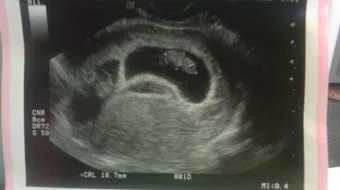

تجدر الإشارة إلى التصوير بالموجات فوق الصوتية عبر المهبل (بالإنجليزية: Transvaginal ultrasound) يكون أكثر دقة من التصوير بالموجات فوق الصوتية عبر البطن (بالإنجليزية: Abdominal ultrasound) في مراحل الحمل المبكرة، وفي العادة يكون ظهور الكيس الحملي (بالإنجليزية: Gestational sac) هو أول علامات الحمل التي تظهر على جهاز الموجات فوق الصوتية (بالإنجليزية: Ultrasound)، حيث يمكن أن يظهر بعد مرور أول 3 أسابيع من الحمل، ويُقدّر معدل قطر كيس الحمل في هذا الوقت بحوالي 2-3 مليمتر، وبعد مرور ما يُقارب خمسة أسابيع ونصف من الحمل يظهر الكيس المُحيّ (بالإنجليزية: Yolk sac) داخل كيس الحمل، ومما ينبغي التنويه إليه أنّ كيس الحمل يظهر في التصوير بالموجات الصوتية عبر البطن عندما ترتفع مستويات هرمون موجهة الغدد التناسلية المشيمائية (بالإنجليزية: Hُuman chorionic gonadotropin) المعروف بهرمون الحمل وتصل إلى ما يقارب 1500 -2000 وحدة دولية/لتر،[2] وهنا نُشير إلى أنّ هرمون موجهة الغدد التناسلية المشيمائية يوجد في الدم منذ بداية حدوث الانغراس (بالإنجليزية: Implantation) للبويضة المخصبة أو الجنين في جدار الرحم،[3] ويمكن الكشف عن هذا الهرمون من خلال إجراء تحاليل واختبارات الحمل، وقد تكشف بعض تحاليل الحمل عن هذا الهرمون في فترة مبكرة بعد مرور حوالي 7 أيام فقط من الإباضة (بالإنجليزية: Ovulation).[4]